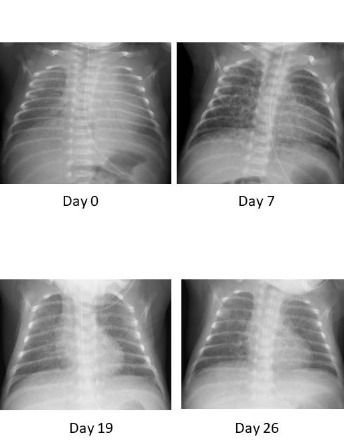

Investigation of urinary β2 microglobulin; substitute for interferon-γ as a suppressor of pulmonary fibrosis in a preterm with chronic lung disease following intrauterine infection

In the respiratory management of preterm infants of less than 33 weeks gestational age and very low birth weight infants, it is essential to understand changes in chest X-ray and blood gas findings in addition to observing their clinical symptoms.